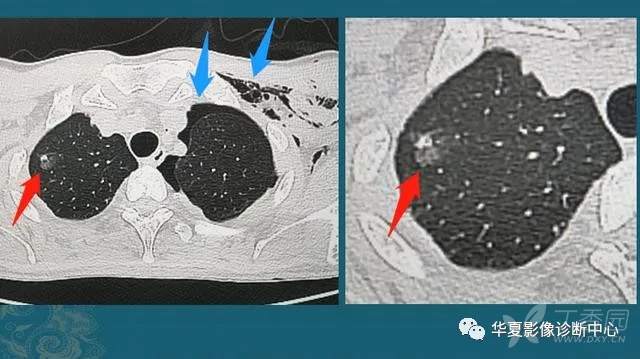

下图是一位30岁年轻人,车祸外伤,撞断3根肋骨,并造成肺挫伤、出血(创伤性湿肺):

红箭头这里的一小片肺组织被车祸撞击暴力撕裂,小血管破裂出血,形成不均匀的高密度影;蓝箭头是气胸和皮下气肿(肺破了,肺里空气溢出到胸腔和肌肉间隙内)。

这种程度的创伤没有生命危险,保守治疗1周出院了,后来小伙子复查CT,肺里留下了一个3mm的光滑小结节:

这是个良性实性小结节,是血肿吸收不彻底形成的,不要紧,不需要定期复查。